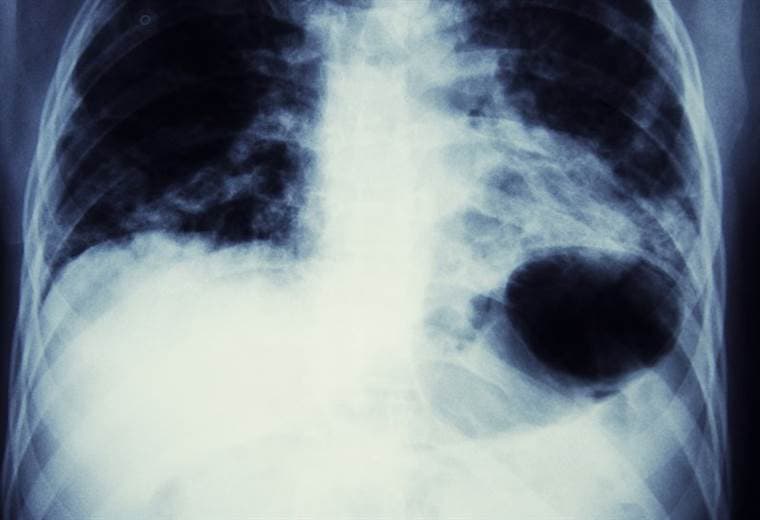

El Radón, un gas radioactivo natural, inodoro, incoloro e insípido, es la causa más importante de cáncer de pulmón después del tabaco, según la Organización Mundial de la Salud (OMS).

La OMS estima que el radón causa entre el 3 y el 14% de todos los cánceres de pulmón en cualquier país.

Según explica la OMS, al respirar las partículas radioactivas del radón se depositan en las células de la superficie de las vías respiratorias, donde pueden dañar su ADN y potencialmente causar cáncer de pulmón.

Distintos estudios en Europa, Estados Unidos y China confirmaron que incluso pequeñas concentraciones de radón, como las que se encuentran en las casas, conllevan riesgos para la salud y "contribuyen significativamente a la incidencia de cáncer de pulmón en todo el mundo".

Por otro lado el riesgo de sufrir cáncer de pulmón para una persona fumadora es mucho mayor cuando lo hace en una zona de alto nivel de radón.

De hecho, según la OMS, los fumadores tienen una vulnerabilidad al radón 25 veces mayor que los no fumadores.